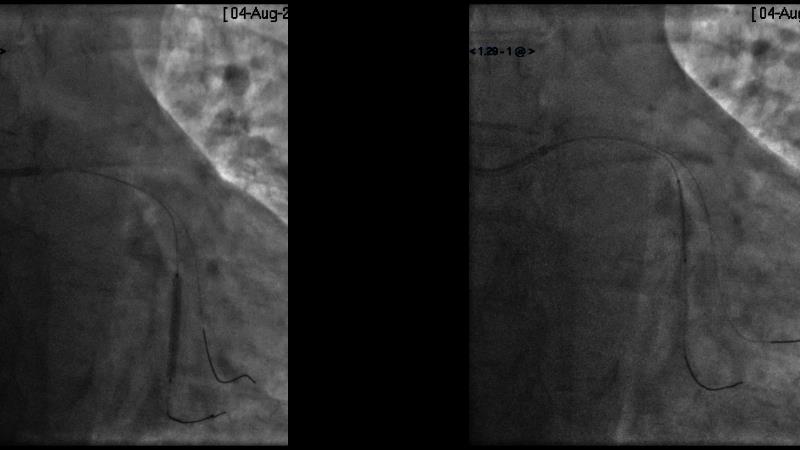

Sirolimus-coated balloon: expanding the scope of indications for complex coronary artery disease treatment

Watch this session to gain case-based insights on using DCBs in complex settings. Learn valuable tips and tricks for optimal DCB application, including the best timing and situations for their use. Discover how to effectively implement a hybrid strategy that combines DES and DCB when needed.